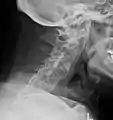

The earliest changes demonstrable by plain X-ray shows erosions and sclerosis in sacroiliac joints. Progression of the erosions leads to widening of the joint space and bony sclerosis. X-ray spine can reveal squaring of vertebrae with bony spur formation called syndesmophyte. This causes the bamboo spine appearance. A drawback of X-ray diagnosis is the signs and symptoms of AS have usually been established as long as 7–10 years prior to X-ray-evident changes occurring on a plain film X-ray, which means a delay of as long as 10 years before adequate therapies can be introduced.[24]

Lateral X-ray of the mid back in ankylosing spondylitis

Lateral X-ray of the neck in ankylosing spondylitis